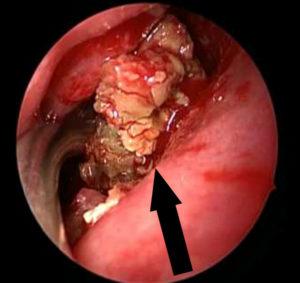

Обратите внимание на изображение воспалительного процесса: